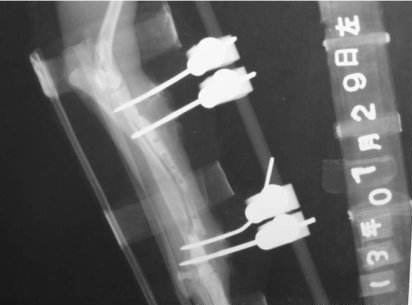

不仅如此,我公司的产品研发部对我们自己生产的PEEK碳纤维骨外固定器零部件进行了对比性实验,证明碳纤维增强PEEK复合材料具有极其优越的X射线穿透能力,这对骨外科病人来说意义重大。因为临床医生不仅需要借助X射线对骨折断端进行修复或固定手术操作,还需要经常检查病人的骨折愈合情况,在此情况下,将长丝碳纤维增强PEEK复合材料作为骨外固定器械材料,在骨外科的临床应用中受到了肯定和欢迎。